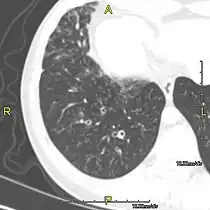

CT image showing dilated and thickened medium-sized airways (bronchiectasis) in a patient with Kartagener syndrome